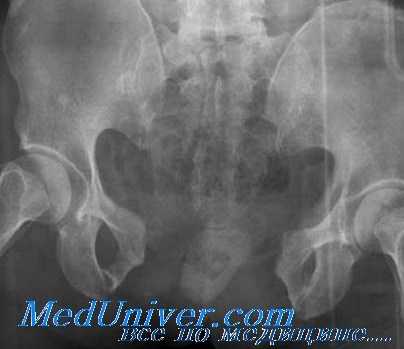

Для определения костного фрагмента обычно достаточно снимка в переднезадней проекции. Неоссифицированные апофизы иногда могут затруднить интерпретацию рентгенограмм, поэтому читателю для внесения ясности в этот вопрос рекомендуем обратиться к началу этой главы.

Рентгенография таза помогает уточнить диагноз, однако в ряде случаев снимков не достаточно для достоверного подтверждения перелома таза, поскольку линию перелома бывает трудно отличить от зоны роста. При возникновении затруднений пациента направляют на МРТ или КТ костей таза. Консультации других специалистов, как правило, не нужны.

Обследование больных с такими переломами таза проводят максимально бережно. Пальпацию осуществляют осторожно, без проверки симптомов Маррея и Вернейля (давления на крылья подвздошных костей). При пальпации выявляется отек и боль. После осмотра выполняют рентгенографию. Перекладывать больного на специальный стол не рекомендуется, поэтому исследование выполняют прямо на каталке. Данные рентгенографии обычно достаточно информативны, МРТ и КТ таза не требуются. При подозрении на сочетанную травму назначают консультации хирурга, уролога, проктолога и других специалистов.

Диагноз перелома костей таза выставляется врачом-травматологом на основании симптомов и данных рентгенографии. При подозрении на «острый живот» и удовлетворительном состоянии пациента проводится наблюдение в динамике. При тяжелом состоянии больного с подозрением на повреждение внутренних органов выжидательная тактика недопустима. Проводится лапароскопия, лапароцентез, иногда - диагностическая лапаротомия. Невозможность самостоятельного мочеиспускания, даже при отсутствии других признаков травмы мочевых путей, является показанием к УЗИ мочевого пузыря и обследованию мочеиспускательного канала. В сомнительных случаях проводят уретрографию.

Для уточнения диагноза выполняют обзорную рентгенографию таза и рентгенографию поврежденного сустава в трех дополнительных проекциях. По возможности пациента направляют на КТ таза, поскольку эта методика позволяет более точно оценить тяжесть травмы и характер смещения отломков. Диагностическая ценность компьютерной томографии возрастает при повреждениях задней колонны и оскольчатых переломах.